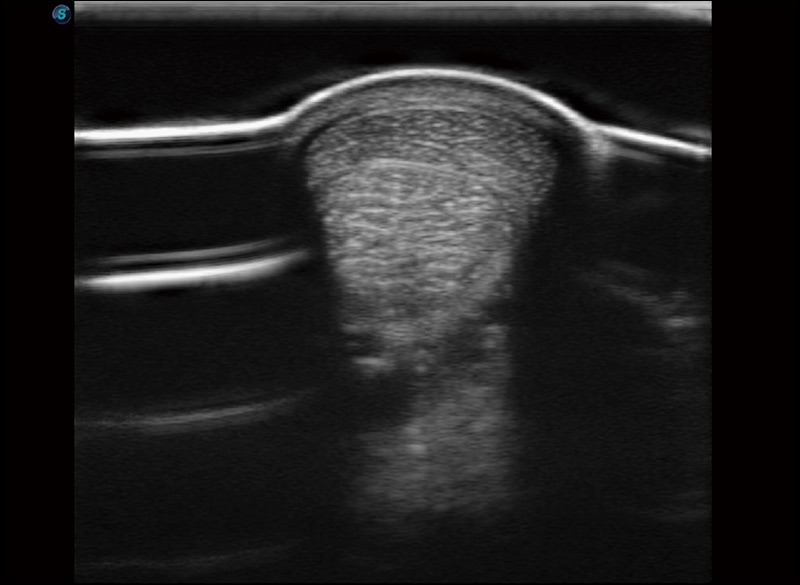

扩展成像

支持线阵和凸阵探头,一键操作即可获得更宽的图像视野

穿刺针增强

高清显示穿刺进针情况